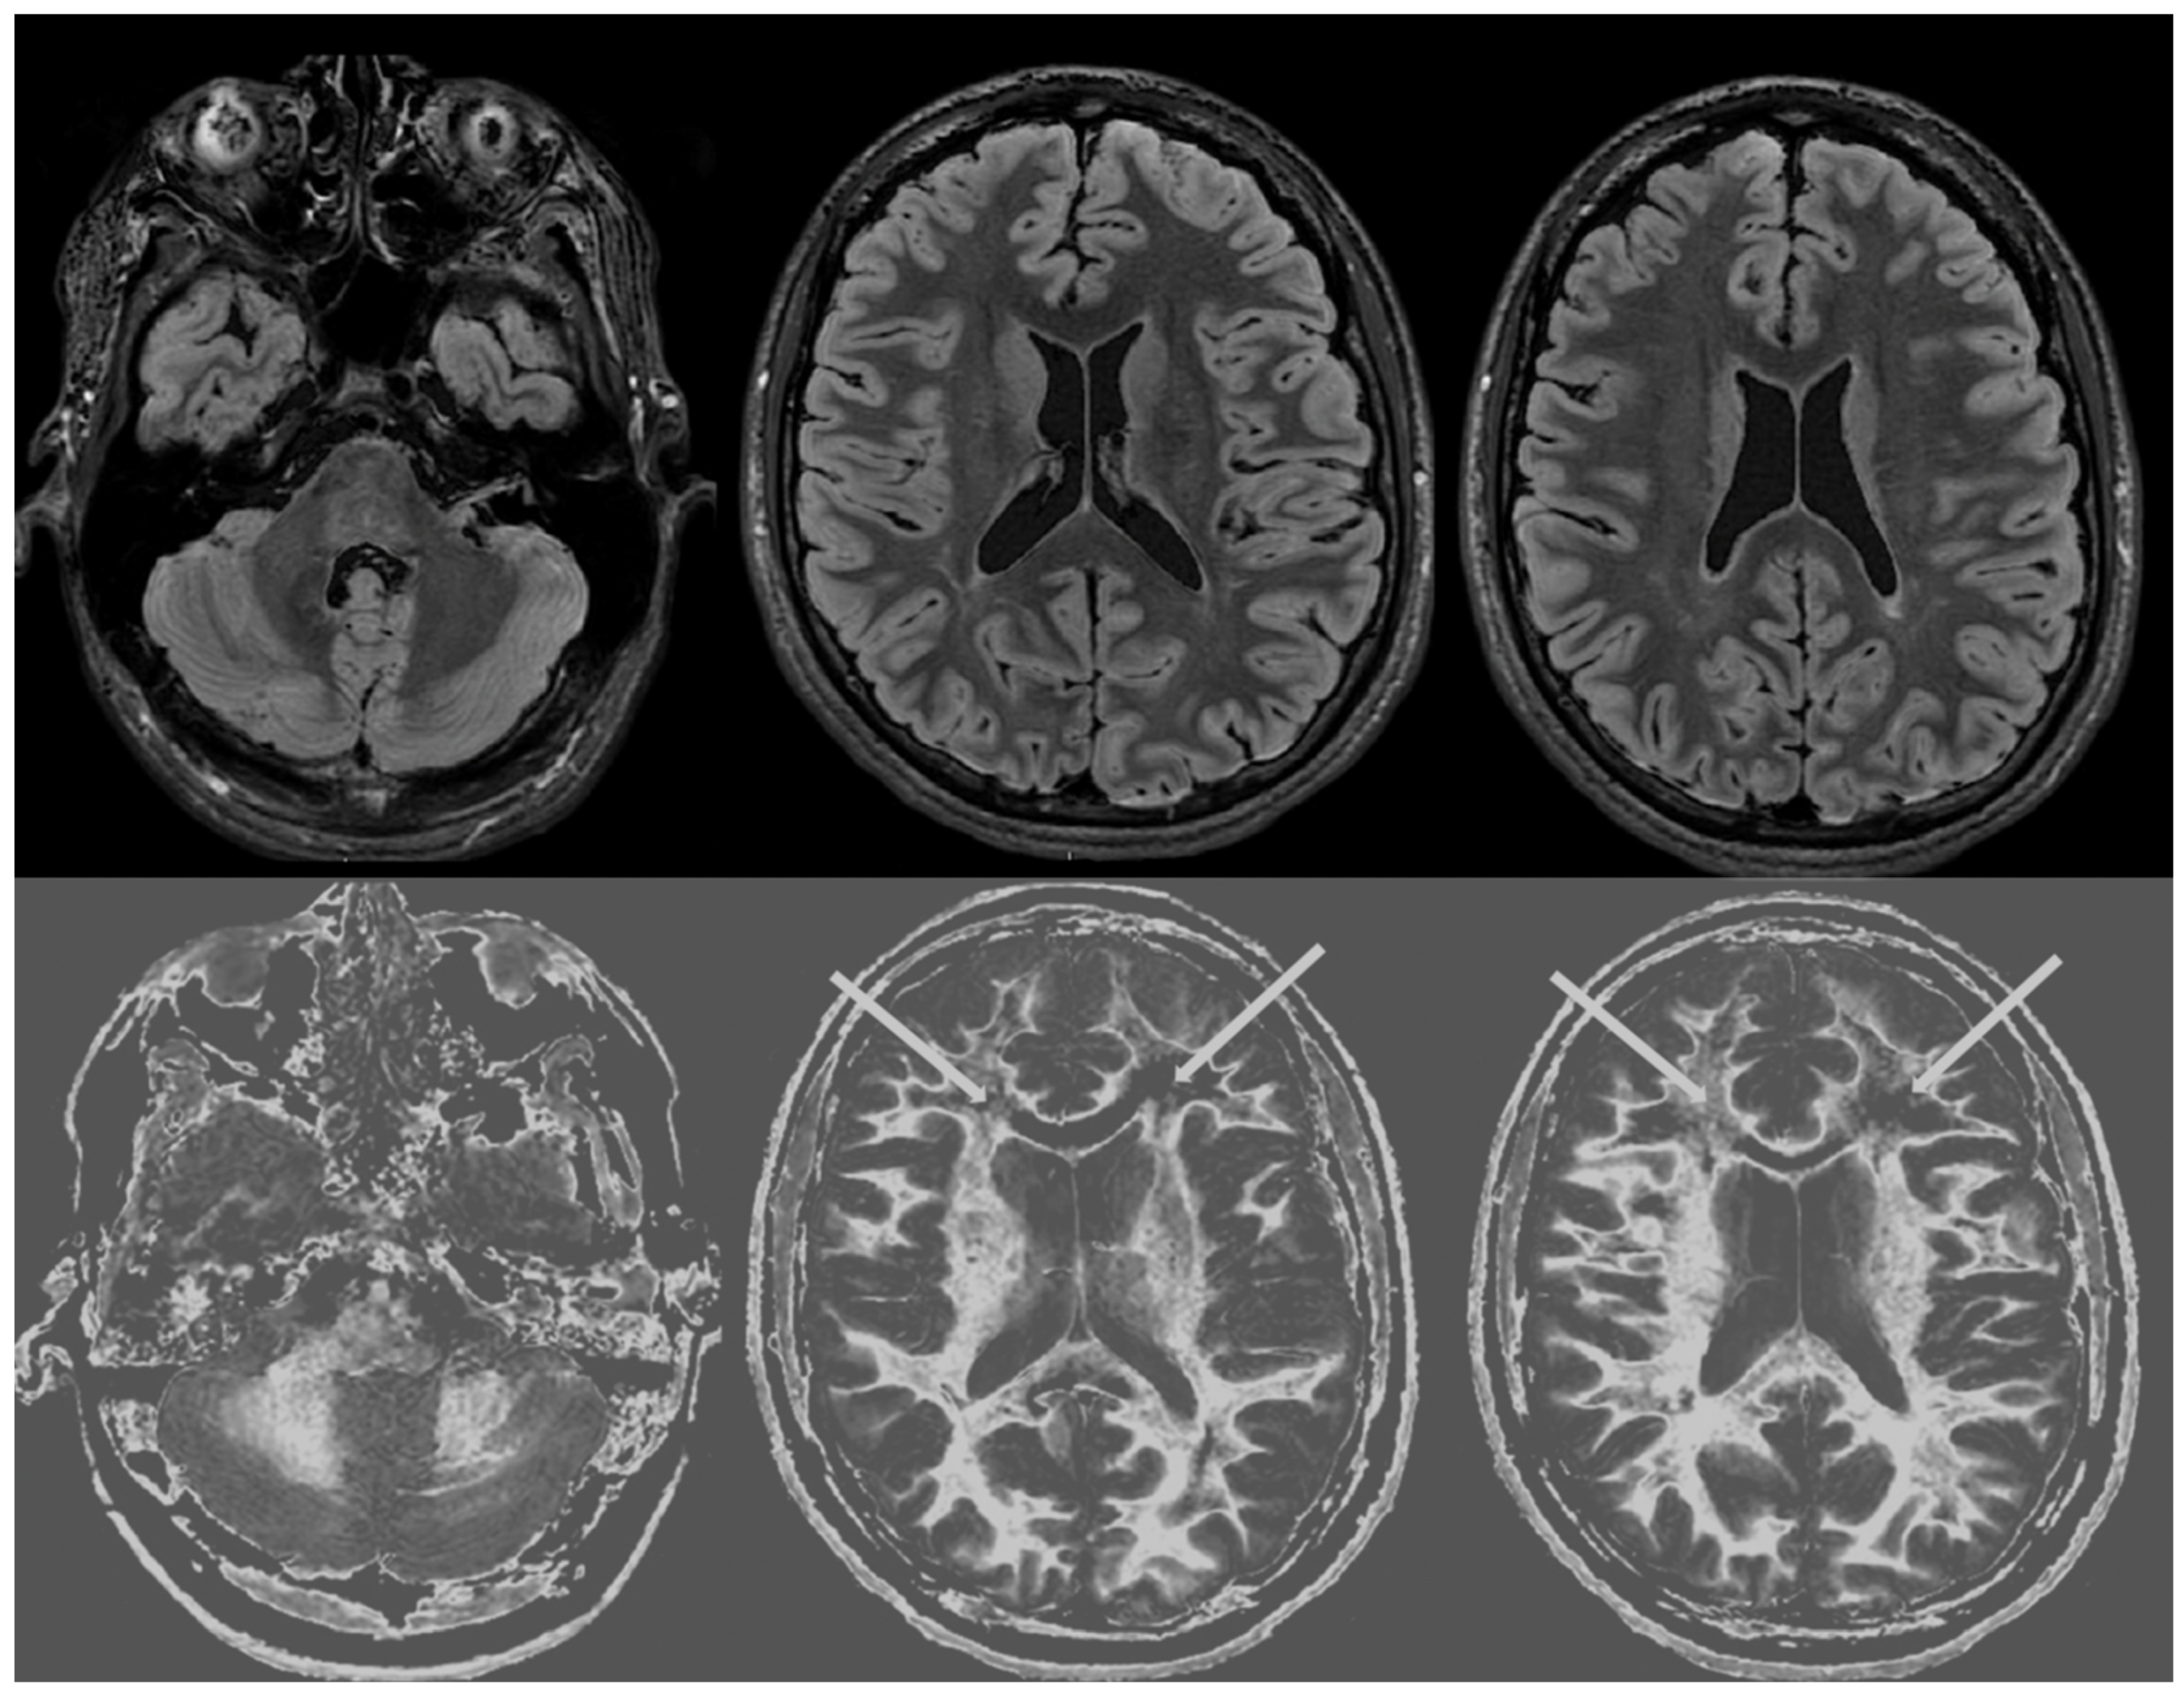

Figure 3 shows narrow mD dSIR images from the normal 18-year-old volunteer. His white matter is normal and shows a low signal (dark) appearance with a mid-grey appearance in and around the corticospinal tracts. Normal high signal boundaries (white lines) are seen at junctions between white and grey matter.

Figure 4 and Figure 5 show T2-FLAIR images (upper rows) with positionally matched dSIR images (lower rows). No abnormality is seen in white matter on the T2-FLAIR images, but very extensive high signal abnormalities are seen in white matter on the corresponding dSIR images. In Figure 4, there is sparing of white matter in the anterior central corpus callosum and adjacent forceps minor, which have a dark appearance (long white arrows). There is also some sparing of the posterior central corpus callosum. In Figure 5, there is sparing of the peripheral white matter of the cerebral hemispheres, which have a dark appearance (long white arrows). Small focal lesions of a relatively increased signal are also seen in the white matter in Figure 5 (grey arrows) on the dSIR images. High signal boundaries between the white and grey matter are seen, but these are less obvious in many areas because of the high signal present in much of the white matter.

Overall, the abnormalities are bilateral and symmetrical and involve most of the white matter of both the cerebral and cerebellar hemispheres. The appearances in the patient are strikingly different from those in the normal control shown in Figure 3, where normal white matter has a low signal (dark appearance), apart from the corticospinal tracts and areas adjacent to them, which are mid-grey.

Figure 4. Case 1 was examined nine months after a severe drug overdose. Comparison of positionally matched T2-FLAIR images (upper row) and narrow mD dSIR images (lower row). No abnormality is seen on the T2-FLAIR image, but there are extensive areas of a high signal in the white matter of the brain. Only the anterior and posterior central corpus callosum and parts of the frontal lobes have a low signal (dark appearance) and look normal on the dSIR images (white arrows) (lower row). High signal boundaries are seen at the junction between the white matter and grey matter but are rendered less obvious in many areas because of the high signal in much of the white matter.

Figure 5. Case 1 was examined nine months after a severe drug overdose. Comparison of positionally matched T2-FLAIR images (upper row) and narrow mD dSIR images (lower row) (higher cerebral hemispheres). No abnormality is seen on the T2-FLAIR images, but there are extensive areas of high signals in the central white matter of the brain (lower row). Only some of the peripheral white matter on the lower images appears dark and looks normal on the dSIR images (white arrows) (lower row). Some other areas of white matter have a mid-grey appearance consistent with a lesser degree of abnormality. Small focal lesions are also seen on the dSIR images (grey arrows) but not on the T2-FLAIR images.